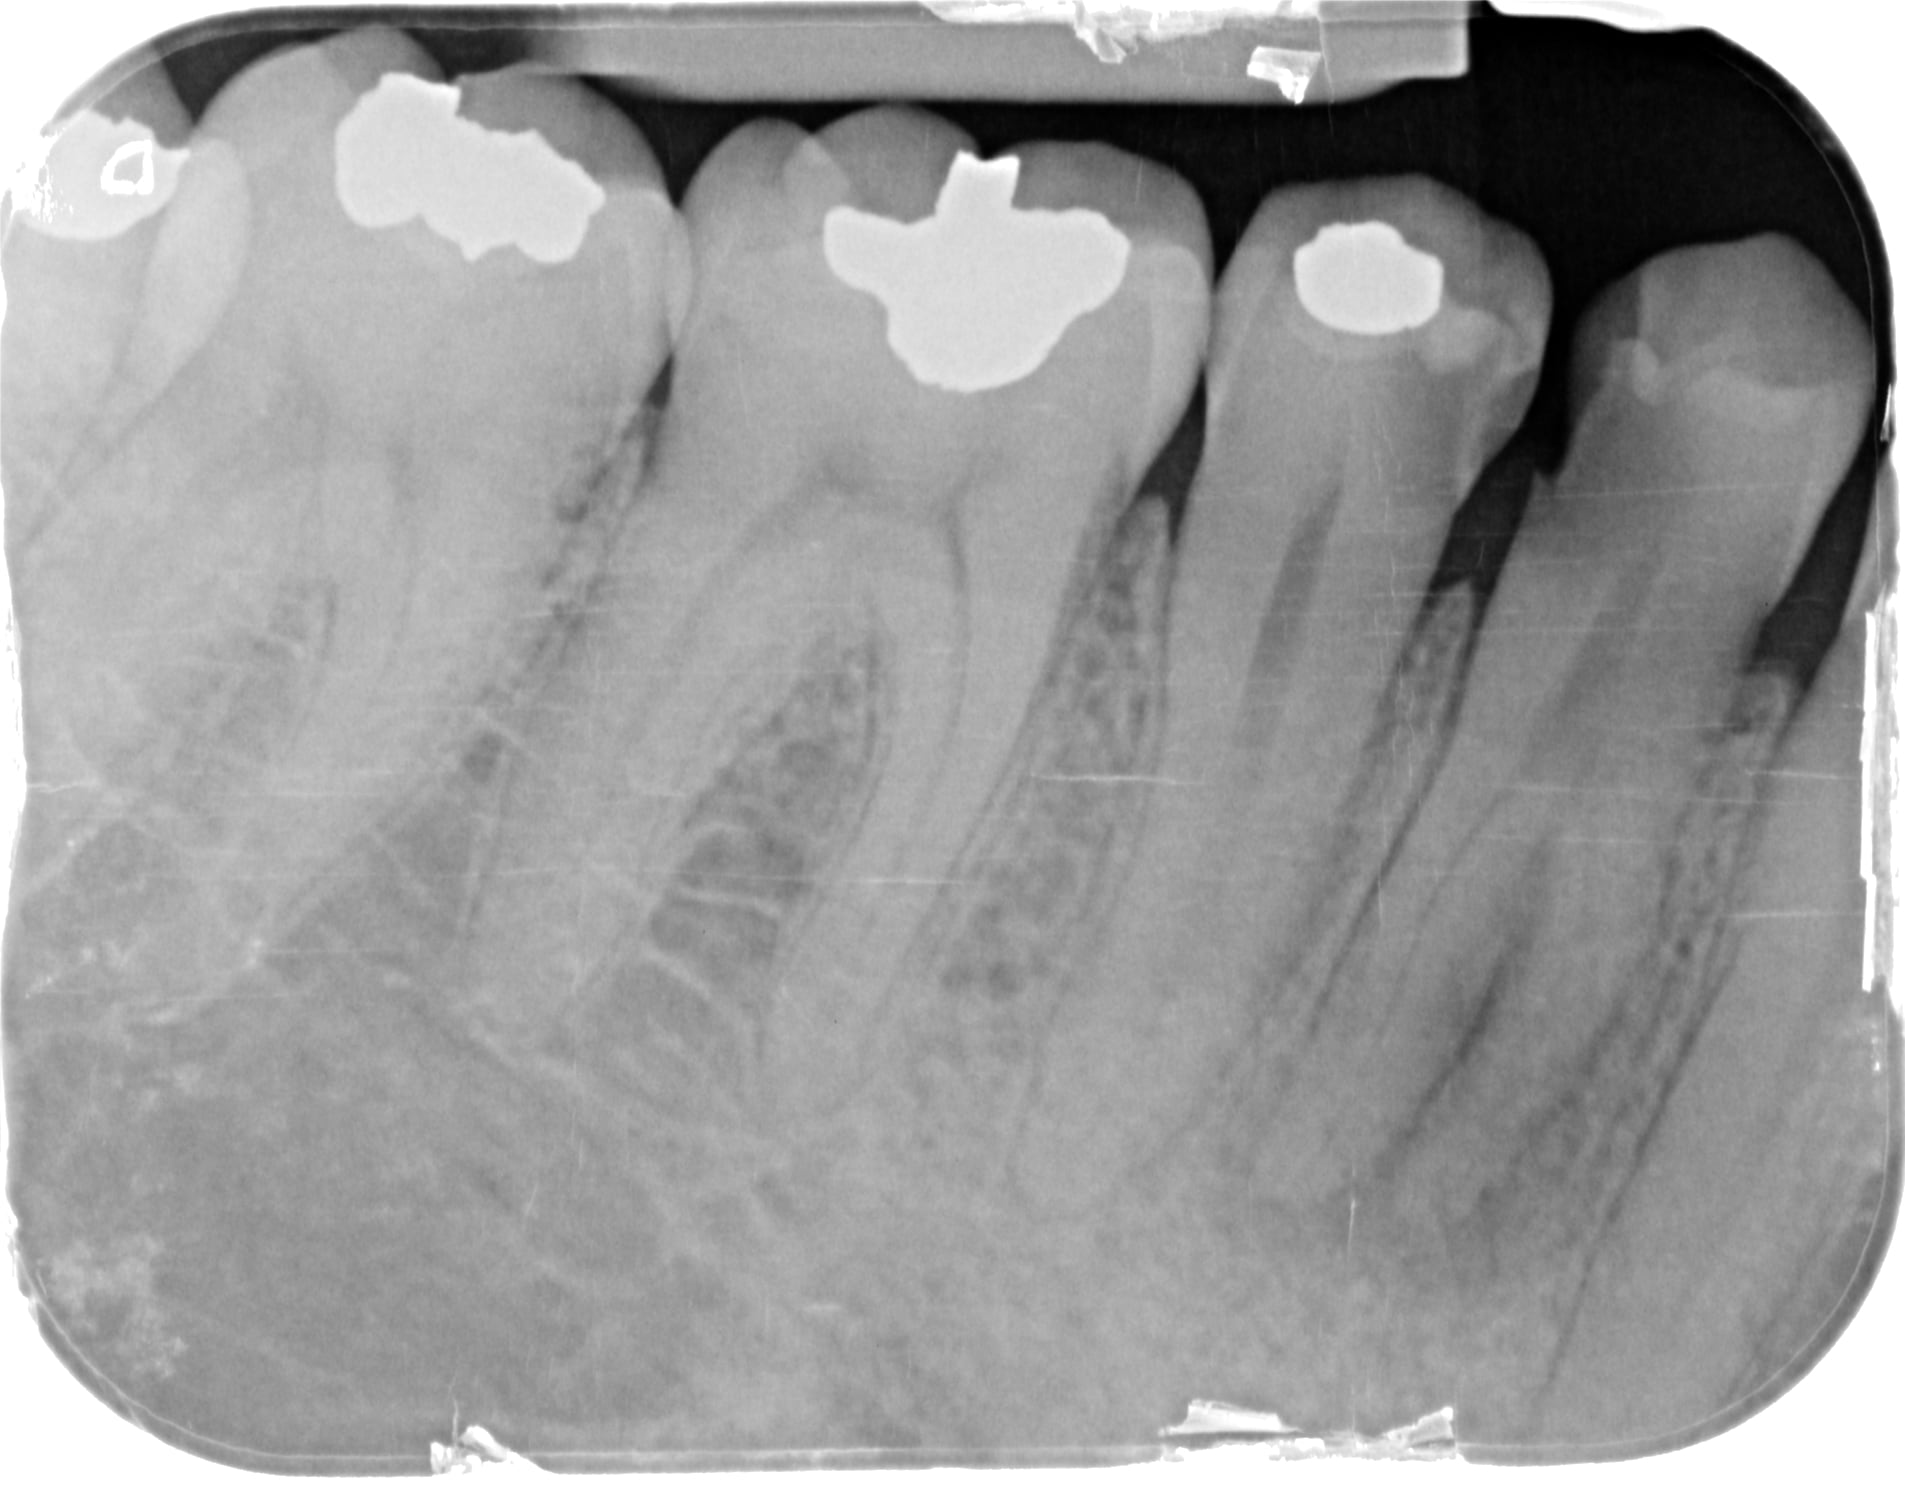

J'ai besoin de votre avis face à cette situation.

Je dénombre au moins 3 apex sur la rétro.

L'endo se tente ? Si oui comment ?

Très atypique, en effet!!

Ca me parait ingérable, sauf à être très délabrant pour l'accès, et donc se retrouver avec une racine inexploitable!

Dommage, ça se tente, en général un canal lingual qui descend tout seul, et deux vestibulaires un peu plus cotons à passer, mais là sur ta radio, ils sont bien visualisables, et l'angulation entrée canalaire/chambre n'est pas à 90°. Un beau challenge.